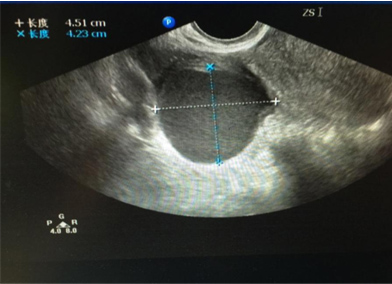

大部分卵巢囊肿都是卵巢排卵后卵巢修复过程中形成的,多随卵巢周期性变化而产生和消失,因此常见于生育年龄的女性。对于卵巢排卵,多数卵巢外观不会出现明显的变化,只有少数情况形成囊肿,一般形成的囊肿也不会太大,一般是一侧卵巢可见囊肿,我们临床医生称之为“生理性囊肿”,并且多数以5cm为界限,也有以8cm为界限。也就是说5cm之内的“生理性囊肿”,我们不需要采取任何措施,囊肿多数会自然消退,持续的时间长短因个人而异,有持续1个月或数月不等,通常会在三个月内自行消失。而对于超过5cm的囊肿,或持续存在,或变大,可能是病理性囊肿,比如卵巢囊性畸胎瘤、各种囊腺瘤,甚至少数是囊腺癌,因此这种情况下,我们建议手术治疗。

此种卵巢“囊肿”,其实不是囊肿,其实是一种良性肿瘤,因囊液粘稠度不同,分为粘液性和浆液性两种,前者囊液如水,后者囊液如果冻,或更稀薄些,B超上可以发现肿瘤呈多房性,囊腺瘤是良性的,但也有交界性肿瘤,也就是介于良性和恶性之间。仅仅依靠B超检查无法区别,因此如果囊肿持续存在,如果B超提示为囊腺瘤,我们也是建议手术。